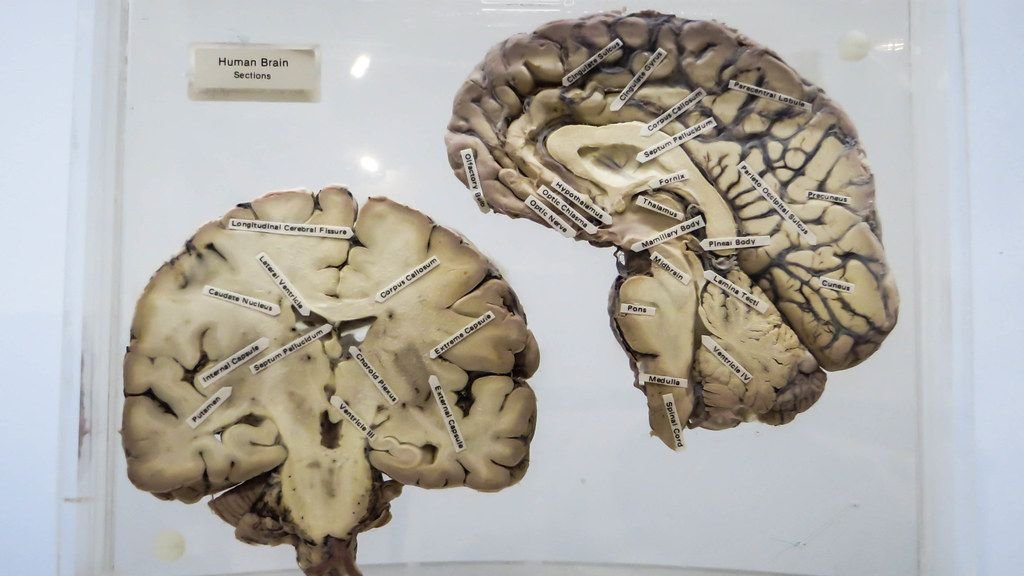

You carry it around every single day, tucked inside your skull, and yet you probably haven’t spent a single moment thinking about just how staggeringly bizarre and powerful it truly is. It weighs roughly three pounds. It looks, honestly, like a wrinkled grey lump. Nothing about its appearance hints at what it actually does.

A Tiny Object With a Cosmic-Scale Architecture

Researchers have investigated the similarities between two of the most challenging and complex systems in nature: the network of neuronal cells in the human brain, and the cosmic network of galaxies. What they found was genuinely startling. The structural similarities between neurons and galaxies are so striking that physicists and neuroscientists have started crossing disciplinary boundaries to study them together.

In the cosmos, galaxies cluster into colossal supergalactic clusters, each stretching over hundreds of millions of parsecs. These mammoth structures exhibit dendritic networks, much like neurons in the human brain. Long filaments connect these galactic nodes, while vast voids punctuate the spaces between them, creating an awe-inspiring celestial web. It’s as if nature has a signature pattern it applies at every scale – from the microscopic connections in your mind all the way out to the large-scale structure of the universe itself.